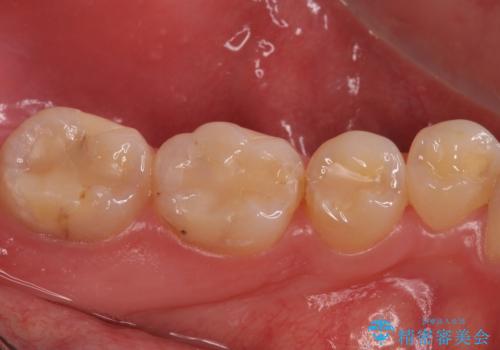

- 左下7 生活歯髄療法:33,000円 仮歯+ジルコニアクラウン:11,000円+121,000円費用は治療当時の料金となります

虫歯が大きくても、今回のように神経を温存することができる場合があります。